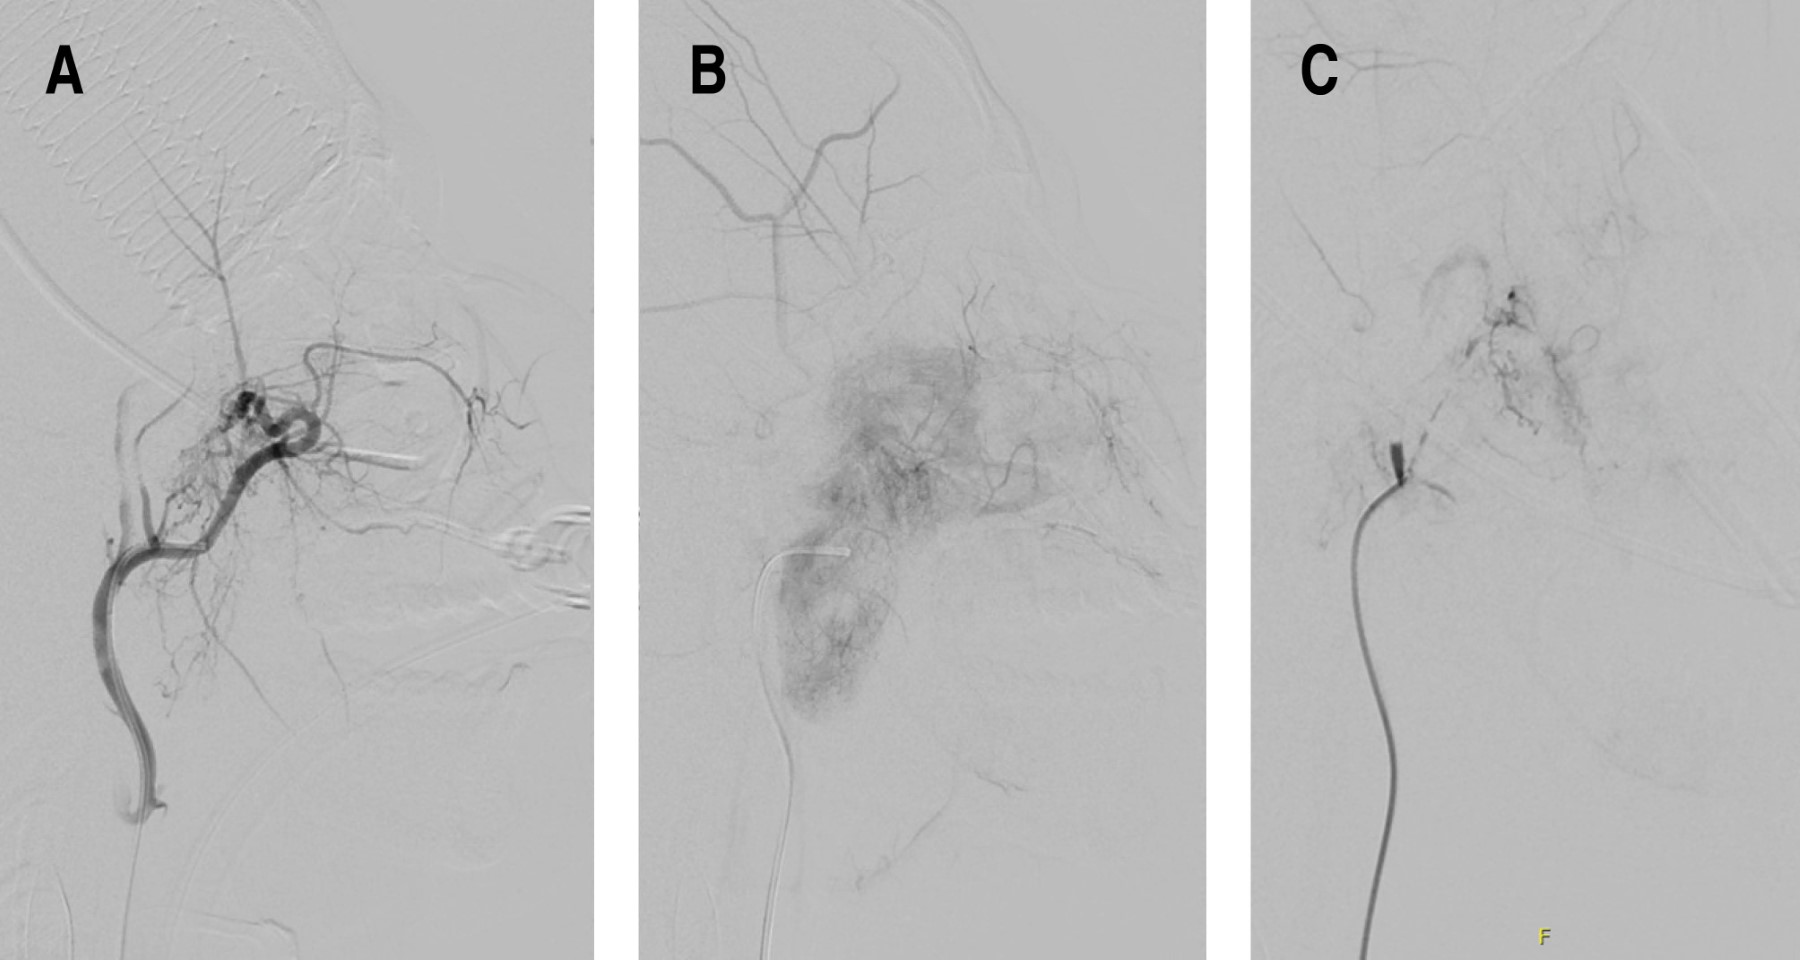

Veinticuatro horas antes, el paciente es llevado a embolización de nasoangiofibroma, accediendo por medio de la arteria femoral común derecha y se observa una irrigación al nasoangiofibroma por parte de la maxilar interna izquierda del 95%, la cual es embolizada con 1 mL de Gelfoam/Lipiodol/esclerol (Figura 5).

Figura 5